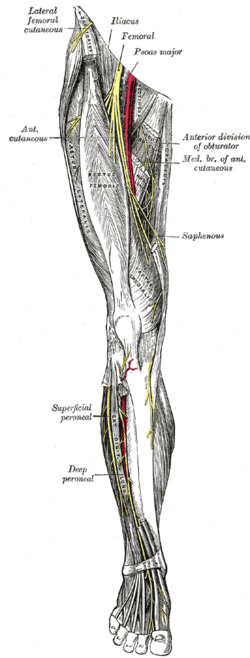

Innervation

The sensory and motor innervation to the lower limb is supplied by the lumbosacral plexus, which is formed by the ventral rami of the lumbar and sacral spinal nerves with additional contributions from the subcostal nerve (T12) and coccygeal nerve (Co1). Based on distribution and topography, the lumbosacral plexus is subdivided into the lumbar plexus (T12-L4) and the Sacral plexus (L5-S4); the latter is often further subdivided into the sciatic and pudendal plexuses:[42]

The lumbar plexus is formed lateral to the intervertebral foramina by the ventral rami of the first four lumbar spinal nerves (L1-L4), which all pass through psoas major. The larger branches of the plexus exit the muscle to pass sharply downward to reach the abdominal wall and the thigh (under the inguinal ligament); with the exception of the obturator nerve which pass through the lesser pelvis to reach the medial part of the thigh through the obturator foramen. The nerves of the lumbar plexus pass in front of the hip joint and mainly support the anterior part of the thigh.[42]

The genitofemoral nerve (L1, L2) leaves psoas major below the two former nerves, immediately divides into two branches that descends along the muscle's anterior side. The sensory femoral branch supplies the skin below the inguinal ligament, while the mixed genital branch supplies the skin and muscles around the sex organ. The lateral femoral cutaneous nerve (L2, L3) leaves psoas major laterally below the previous nerve, runs obliquely and laterally downward above the iliacus, exits the pelvic area near the iliac spine, and supplies the skin of the anterior thigh.[43]

The obturator nerve (L2-L4) passes medially behind psoas major to exit the pelvis through the obturator canal, after which it gives off branches to obturator externus and divides into two branches passing behind and in front of adductor brevis to supply motor innervation to all the other adductor muscles. The anterior branch also supplies sensory nerves to the skin on a small area on the distal medial aspect of the thigh.[44] The femoral nerve (L2-L4) is the largest and longest of the nerves of the lumbar plexus. It supplies motor innervation to iliopsoas, pectineus, sartorius, and quadriceps; and sensory branches to the anterior thigh, medial lower leg, and posterior foot.[44]

The nerves of the sacral plexus pass behind the hip joint to innervate the posterior part of the thigh, most of the lower leg, and the foot.[42] The superior (L4-S1) and inferior gluteal nerves (L5-S2) innervate the gluteus muscles and the tensor fasciae latae. The posterior femoral cutaneous nerve (S1-S3) contributes sensory branches to the skin on the posterior thigh.[45] The sciatic nerve (L4-S3), the largest and longest nerve in the human body, leaves the pelvis through the greater sciatic foramen. In the posterior thigh it first gives off branches to the short head of the biceps femoris and then divides into the tibial (L4-S3) and common fibular nerves (L4-S2). The fibular nerve continues down on the medial side of biceps femoris, winds around the fibular neck and enters the front of the lower leg. There it divides into a deep and a superficial terminal branch. The superficial branch supplies the peroneus muscles and the deep branch enters the extensor compartment; both branches reaches into the dorsal foot. In the thigh, the tibial nerve gives off branches to semitendinosus, semimembranosus, adductor magnus, and the long head of the biceps femoris. The nerve then runs straight down the back of the leg, through the popliteal fossa to supply the ankle flexors on the back of the lower leg and then continues down to supply all the muscles in the sole of the foot.[46] The pudendal (S2-S4) and coccygeal nerves (S5-Co2) supply the muscles of the pelvic floor and the surrounding skin.[47]

Nerves of the right lower extremity Posterior view.